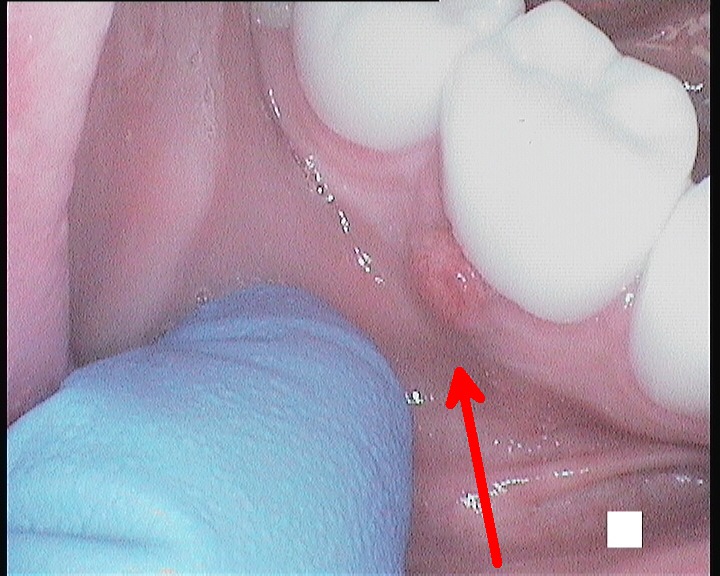

Before commencing the treatment, a local anaesthetic is administered and later a protective non-latex rubber sheet is placed around the tooth to prevent saliva contaminating the tooth and at the same time improves patients comfort.